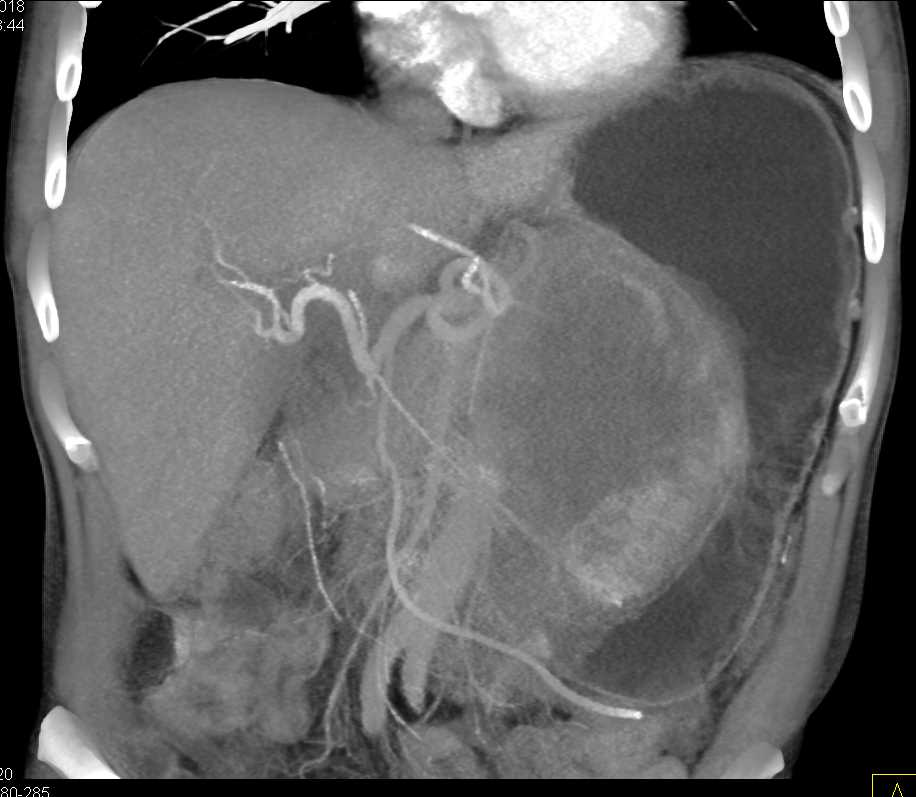

Lagre Gastric GIST Tumor